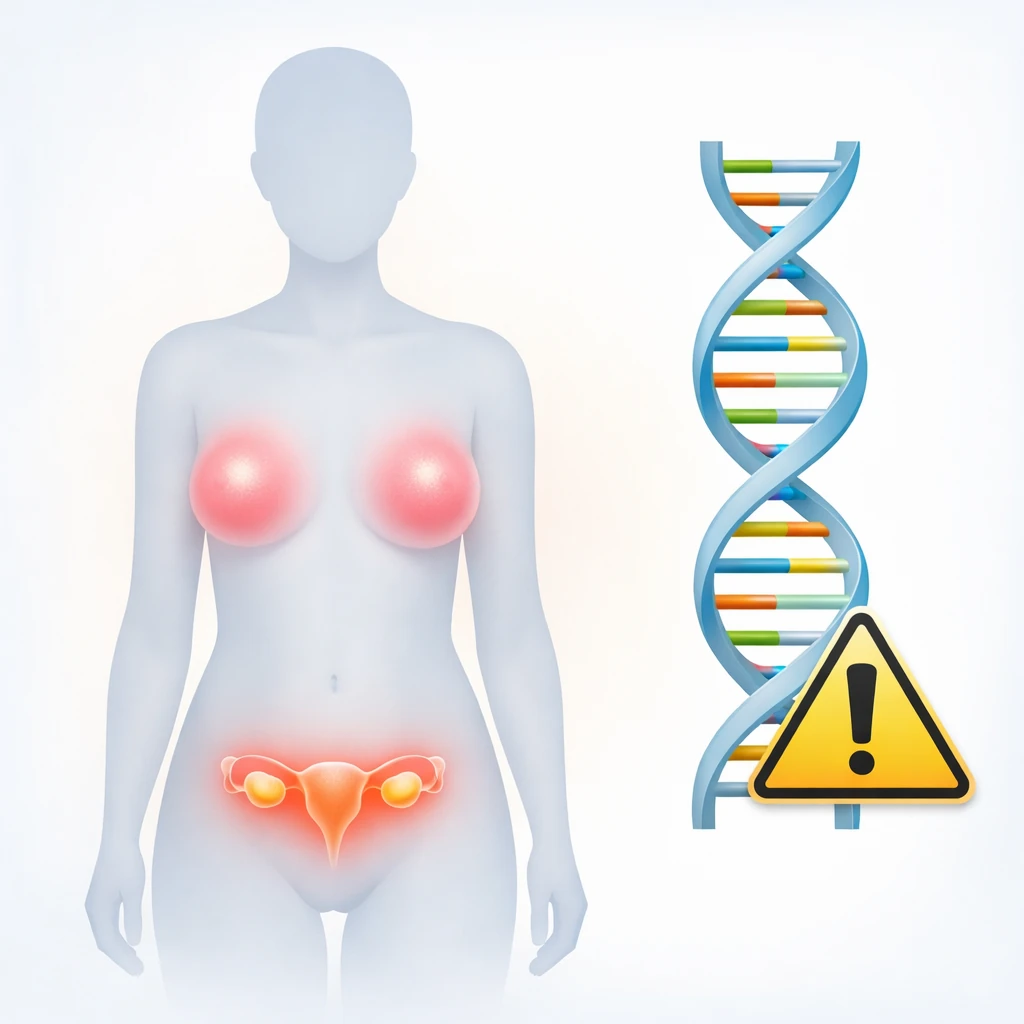

آنتیژن کارسینوم سلول سنگفرشی (SCC) یک نشانگر زیستی (بیومارکر) است که در تشخیص، پایش و ارزیابی پیشآگهی برخی از سرطانها، بهویژه سرطانهای سلول سنگفرشی، کاربرد دارد. این نشانگر در سرطانهای دهانه رحم، پوست، ریه، سر و گردن و مری مورد استفاده قرار میگیرد. در این مقاله به بررسی ویژگیها، کاربردهای بالینی و محدودیتهای SCC پرداخته میشود.

- دهانه رحم: در سرطان دهانه رحم، سطح SCC اغلب با اندازه تومور، مرحله بیماری و احتمال عود مرتبط است. در بسیاری از بیماران، افزایش SCC پیش از ظهور علائم بالینی عود، مشاهده میشود.